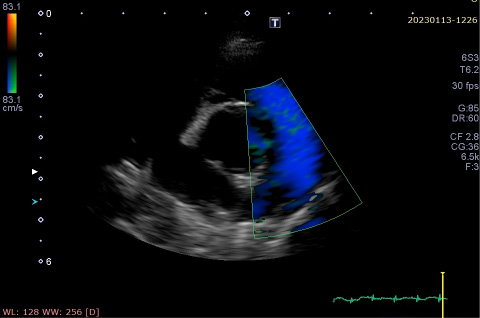

手術前(カラーモザイク状に見える部分が動脈管の血流)

手術後(動脈管の血流が消失している)

手術前(カラーモザイク状に見える部分が僧帽弁逆流)

手術後(僧帽弁逆流が消失している)